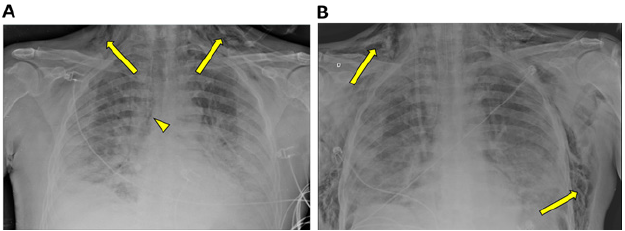

Figure 1A: Chest X-ray obtained on day 13 of hospitalization. The image shows cervicothoracic subcutaneous emphysema (arrow) and signs of pneumomediastinum (arrowhead). In addition, extensive bilateral consolidative opacities and small bilateral pleural effusion are also noted.

Figure 1B: Chest x-ray obtained after the patient was admitted to the ICU and orotracheal intubation and mechanical ventilation. The image shows an increase in subcutaneous emphysema (arrow), evolving with thoracic extension.